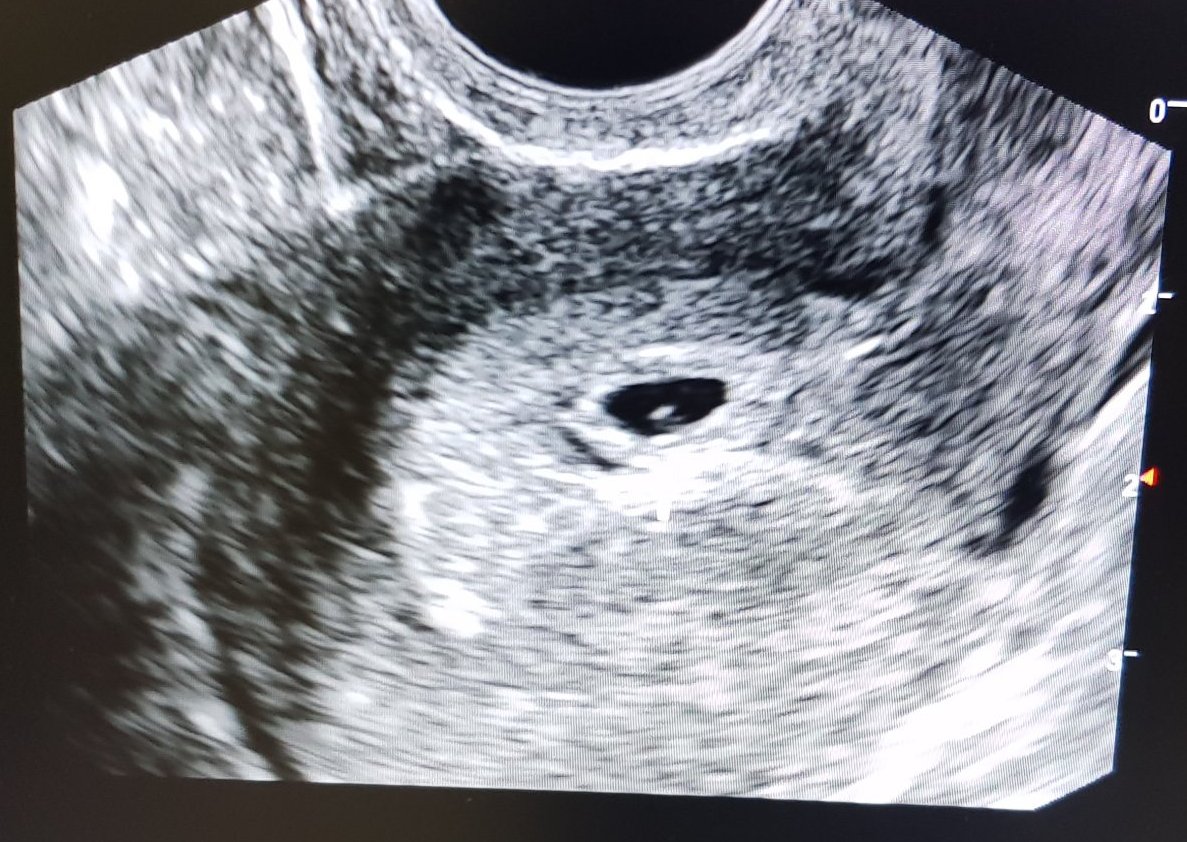

аз съм в 4г.с + 5 дни и до сега си имаме видяно сакче, в края на месеца сме отново на преглед. За сега и аз това се питам относно симптомите...хм..единствено гърдите ми са леко болезнени, но не е непоносимо. Заспивам по-рано от обичайното, но не знам дали не е просто от времето това. Та се чудех дали е рано просто са симптоми или..знам ли и аз